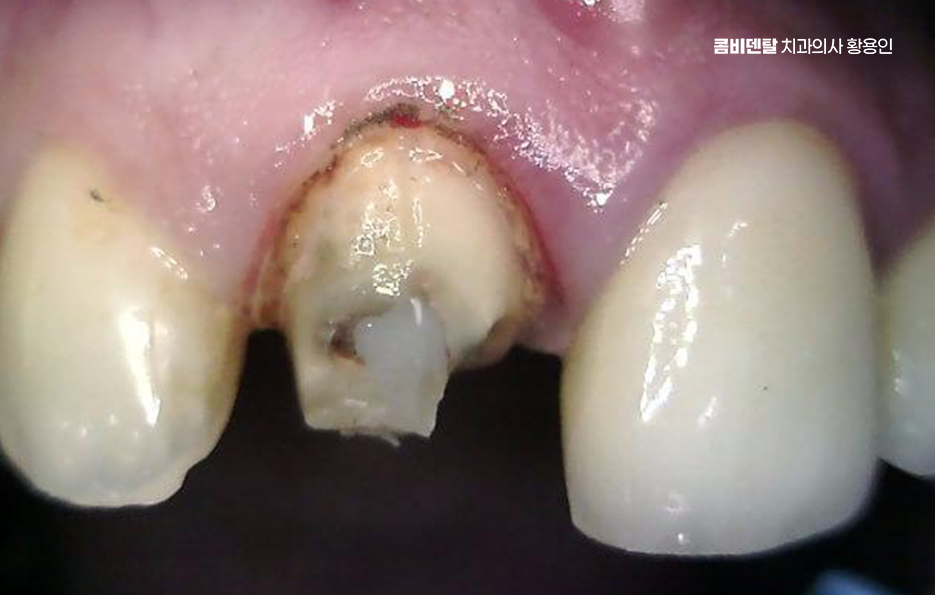

앞니는 웃을 때, 말할 때 먼저 보이는 자리여서 과거에는 심미성만 우선해서 치료를 하거나, 그 당시 기술로 가능한 선에서만 보철을 해둔 경우가 많은데 시간이 지나면 잇몸이 내려가면서 보철물 가장자리가 드러나거나 회색 선이 드러나는 경우나 2차 충치 등의 문제가 나타날 수 있었어요

이런 경우 처음엔 잇몸이 붓거나 피가 나는 가벼운 증상으로 시작될 수 있지만 그 아래에서는 이미 보철물 안쪽 치아가 썩고 있거나, 보철물 아래 충치가 진행됐을 수 있으며 특히 오래된 보철물은 접착제가 이미 닳아 있거나 밀착력이 떨어져 있어서 세균이 쉽게 침투할 수 있어서 이런 식의 2차 충치는 눈으로 보이지 않기 때문에, 문제가 꽤 심각해졌을 때야 느끼게 되는 경우가 많은 거예요

문제가 심해지면 결국 신경에까지 세균이 도달해서 통증이 생기고 찬물에 시리거나, 저리듯이 쑤시는 느낌, 잇몸에 작은 뾰루지가 생기는 경우도 있으며 그냥 손가락으로 눌렀을 때 묵직한 압통이 있다면 이미 신경치료가 필요한 상태일 가능성이 높아지고 이런 경우엔 기존 보철물을 제거하고, 내부 충치 상태를 확인한 뒤, 신경치료부터 들어가야 할 수 있었어요